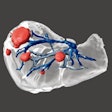

3D printing makes giant strides in liver